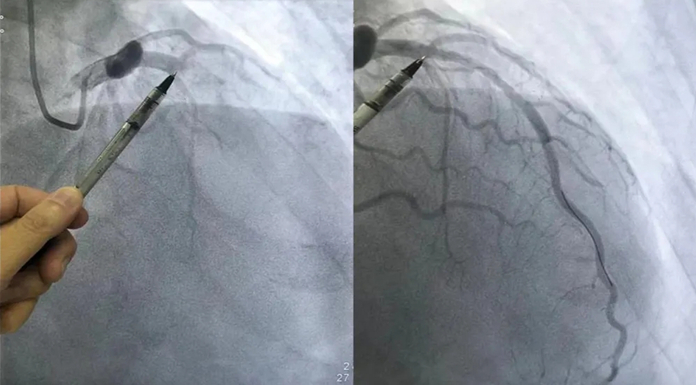

9月11日,西藏大学附属阜康医院邀请华医心诚医生集团专家团队举行座谈会,就阜康医院内科尤其是心血管学科建设,以及即将开展的“西藏人人健康”项目,建言献策,提出了宝贵建议。在此前一天,国家院士专家进藏义